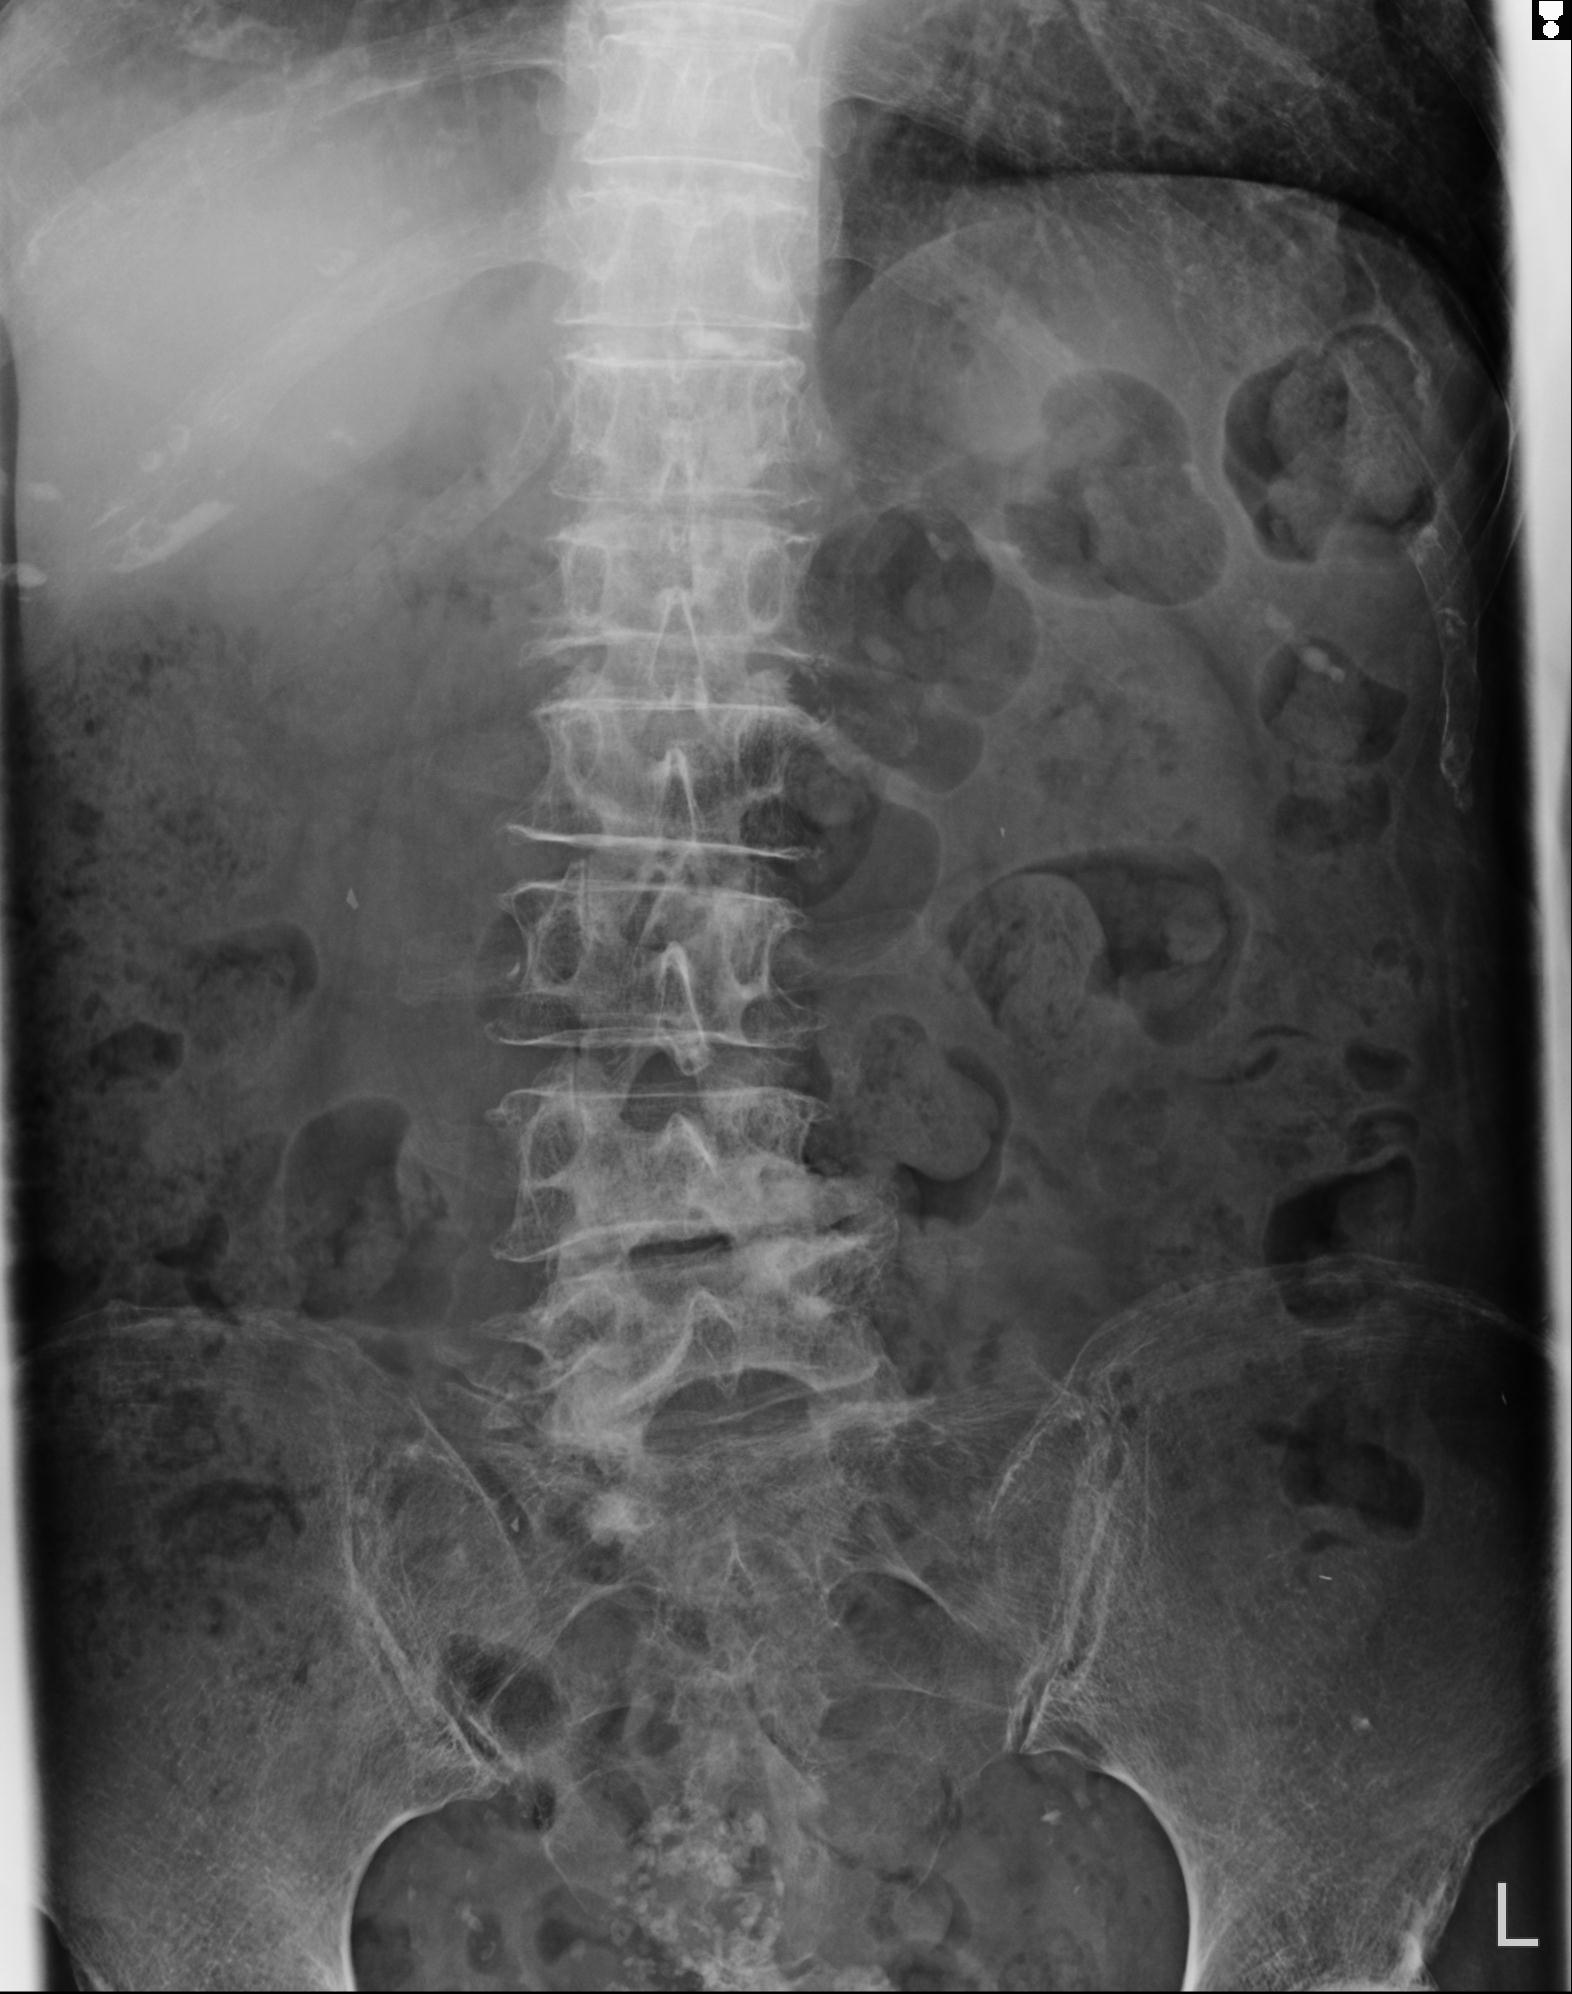

102916 2/1 と 3/22 腰椎 2R 74歳女性 LIFX